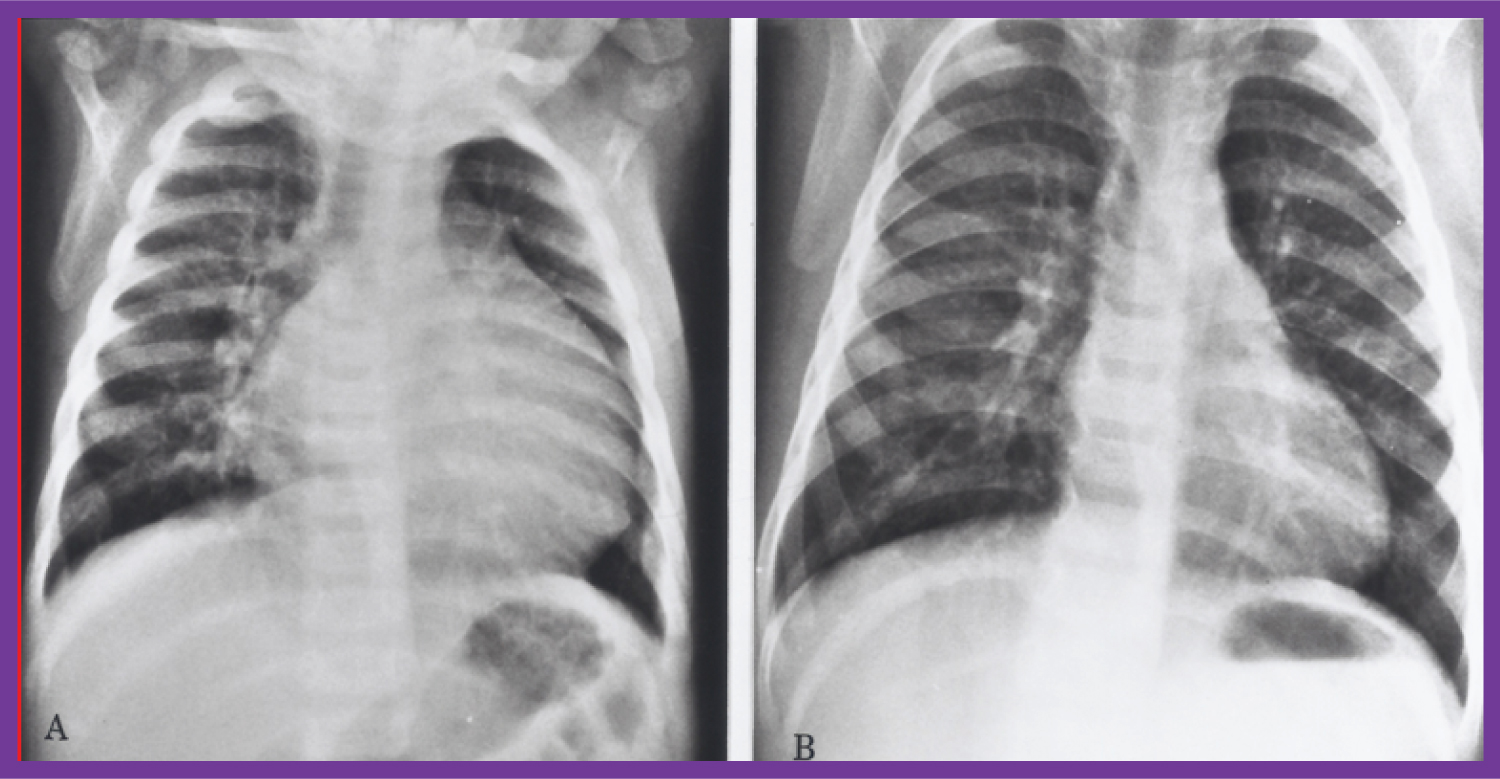

Figure 8: Chest X-rays in antero-posterior view, prior to A) and following B) Hydralazine therapy. A) Moderate cardiomegaly and pulmonary venous congestion were seen prior to therapy; B) Which improved remarkably after therapy [1]. View Figure 8

Other contributions are: Review of evaluation of left ventricular function by echocardiography [26,27], echocardiographic diagnosis of tricuspid atresia [28], utility of contrast echocardiography in the assessment of hypoxemia after open heart surgery [29], quantifying left ventricular muscle mass by m-mode echocardiograms in children [30], racial and sexual differences in echo measurements in children [31], heart size and function in children with sickle cell disease [32], and afterload reduction in the treatment of primary myocardial disease (Figure 6, Figure 7 and Figure 8) [33].